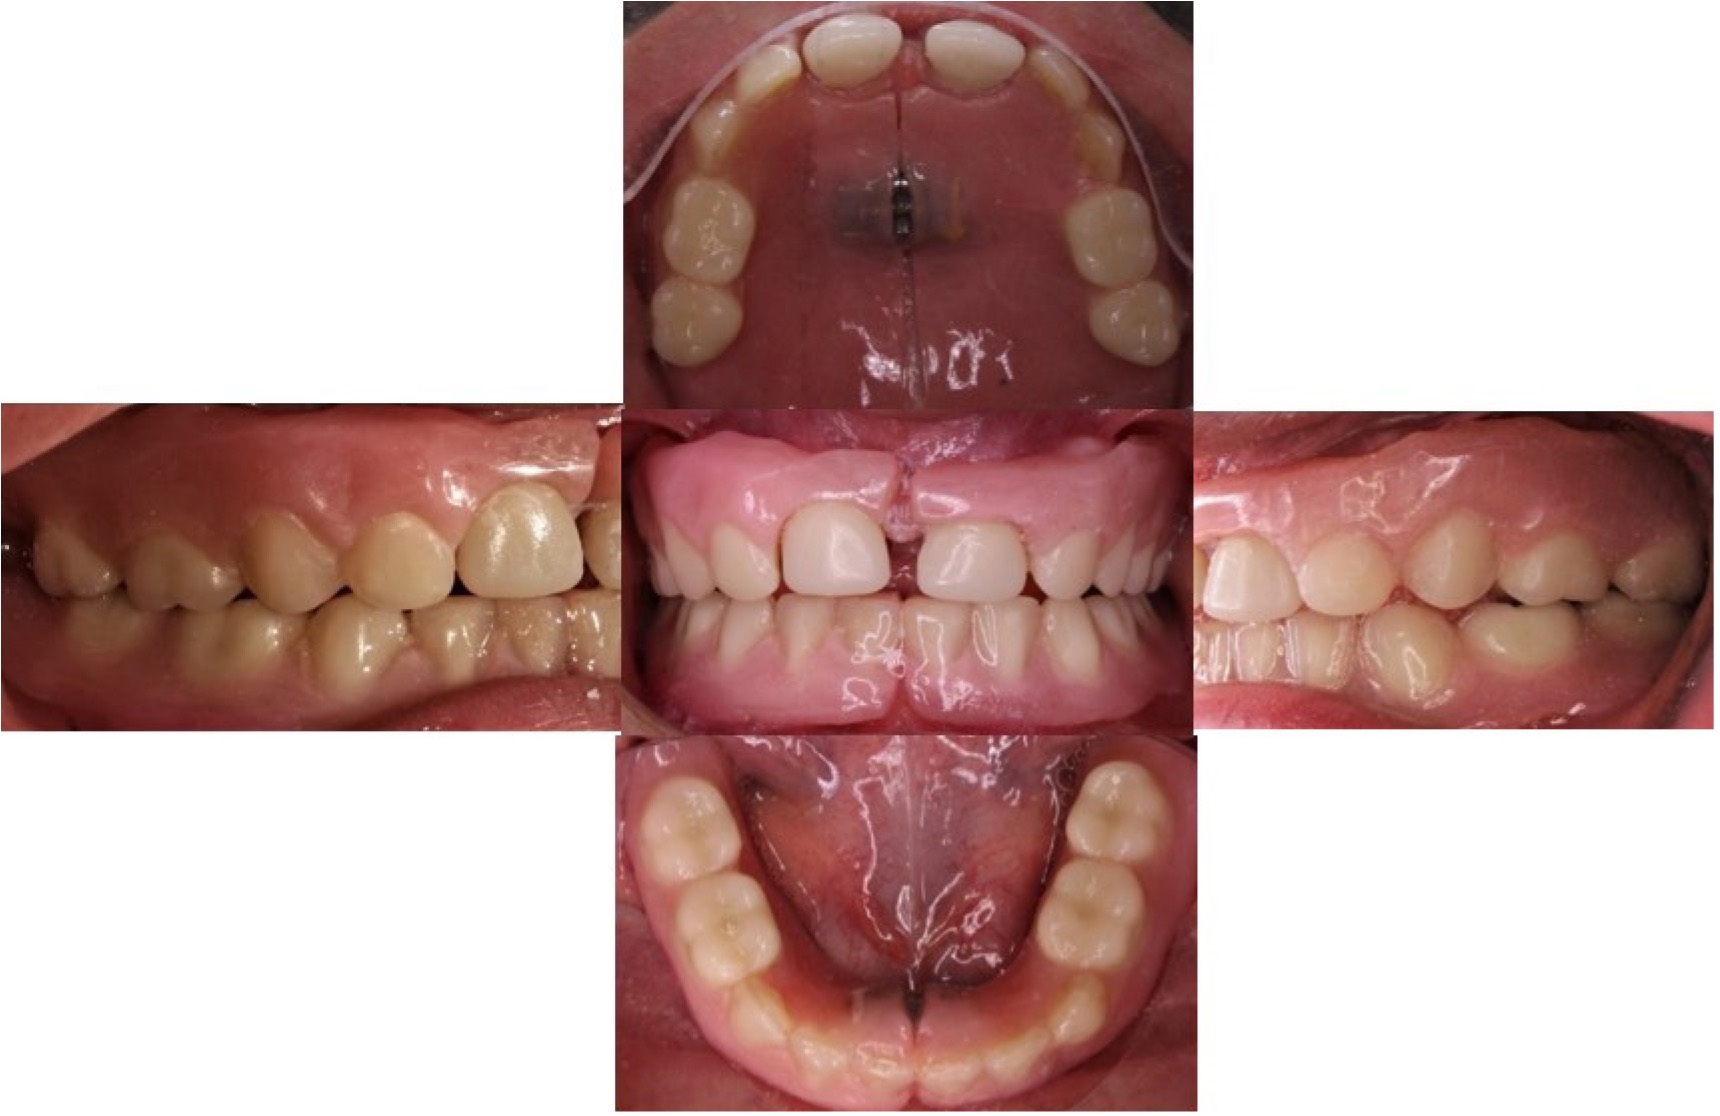

En el examen clínico intraoral se observa Anodoncia Parcial Verdadera con presencia únicamente de los dientes 52 y 62 de forma cónica, reborde alveolar atrófico y estrecho y disminución de la dimensión vertical (Figura 2). En la ortopantomografía se observa la ausencia de todos los gérmenes dentarios permanentes con excepción de los dientes 11 y 21 en forma cónica (Figura 3) (Tabla 1).

Figura 2: Fotografías intraorales iniciales.